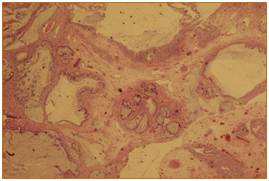

A complete blood count, liver function test, urine culture and PSA were all within normal ranges. Urine cytology revealed atypical cells. CT abdomen and pelvis with I.V contrast showed a 3.1 x 2.4 x 3 cm polypoidal mass of the trigone (Figure 1). Afterwards, the patient underwent cystoscopy which showed a solid florid mass extending from the trigone to the posterior wall of the urinary bladder, TURBT was carried out. The Histopathology slides showed cystitis cystica with cystitis glandularis (Colonic metaplasia) (Figure 2‒5).

Figure 5 Complex glandular structure with mucin producing cells and mucin extravasation.